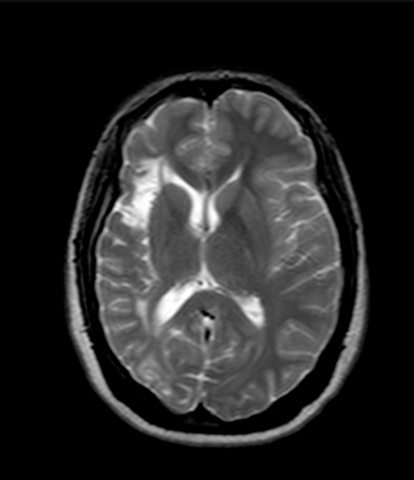

Лікар-рентгенолог оцінює не лише наявність патологій, а й загальну «картину» мозку. Є кілька ключових критеріїв, які вказують на норму.

- Симетрія півкуль. У здорової людини права і ліва півкулі мозку мають бути симетричними. Це означає, що їх форма, розміри та структура приблизно однакові. Невелика природна асиметрія допустима, але значні відмінності можуть свідчити про набряк, пухлину, наслідки травми або інсульту.

- Стан шлуночків мозку. Шлуночки — це порожнини всередині мозку, заповнені спинномозковою рідиною. У нормі вони мають стандартні розміри і чіткі контури. Якщо шлуночки розширені, це може бути ознакою:

Зменшені або деформовані шлуночки також можуть вказувати на патологічні процеси.

Тож, МРТ головного мозку — це потужний інструмент, який дозволяє виявити навіть найменші зміни. Симетрія півкуль, нормальний стан шлуночків і відсутність значущих вогнищ — ознаки здорового мозку.